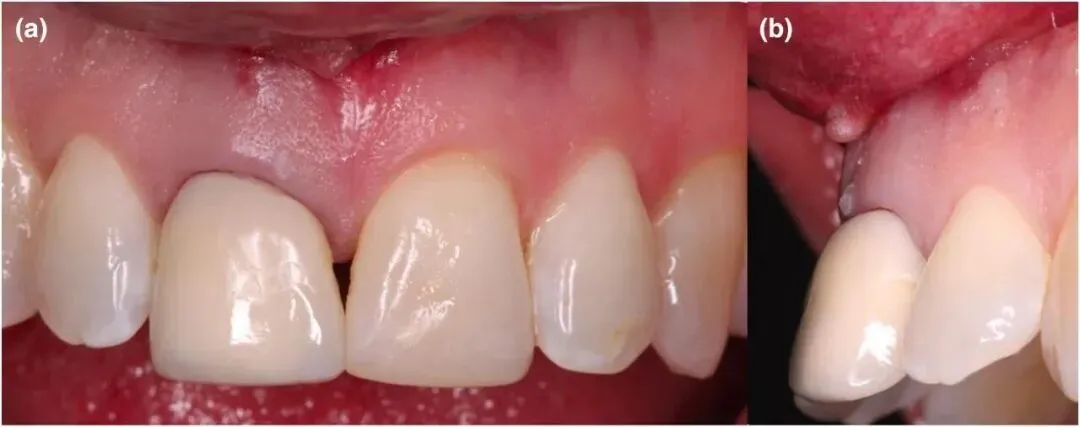

图1 口内拔牙前照片

• 术前CBCT显示:11牙位点为4型水平牙槽骨缺损,骨缺损体积336.28mm³,PES(软组织美学评分)仅4分、WES(修复体美学评分)2分(美学基础极差);

图2 11牙(右上中切牙)拔除后骨质破坏严重(图中红框所示区域)